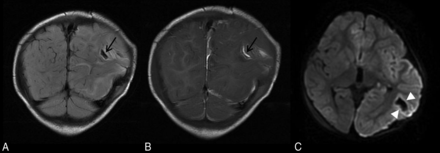

Parenchymal brain lacerations. Case 135. Coronal T2 FLAIR (A) and T1WI (B) demonstrate a curvilinear cleft (black arrows) in the left posterior temporoparietal region containing blood products consistent with acute laceration. C, Axial DWI demonstrates marginal diffusion hyperintensity (white arrowheads).

Of the 18 cases of patients with AHT with lacerations, 7 (39%) demonstrated multiple lacerations. Most lacerations were hemorrhagic linear tears or clefts in the subcortical white matter (SCWM) (Fig 1). Lacerations were present in various regions, with frontal lobes predominating. In half of the cases (9/18), lacerations were suspected on NCCT (generally lesions longer than 1.5 cm or fluid-filled clefts), whereas the remaining were only identified by MR imaging. MR imaging characteristics include GRE blooming or diffusion restriction along the margins of the tear or a cleft with a fluid-hematocrit level (Figs 2 and 3). A few lacerations were surrounded by vasogenic edema. The On-line Table summarizes imaging characteristics of lacerations and details on which particular MR imaging sequence the lacerations were optimally visualized.